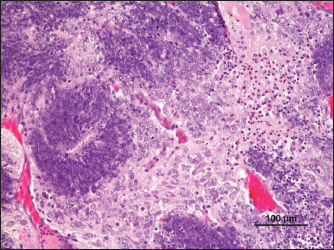

Fig. 4. Bone (*), cartilage (white arrow), and respiratory epithelium (black arrow) (H&E).

The mass presented areas of epidermal differentiation with laminated keratin and sebaceous glands. Cell differentiation into digestive and respiratory epithelium, bone, cartilage, and vast areas of differentiation into nervous tissue were also present (Figs. 37). Moreover, the nervous tissue presented focal areas of ependymoma. Epithelial areas with hypercellularity, cell atypia, stromal microinvasion, hemorrhages, and necrosis were also observed. Metastatic epithelial cells were detected invading the pancreas, the small intestine serosa, and the mesenterium. Therefore, the mass was classified as a malignant teratoma with abdominal carcinomatosis.